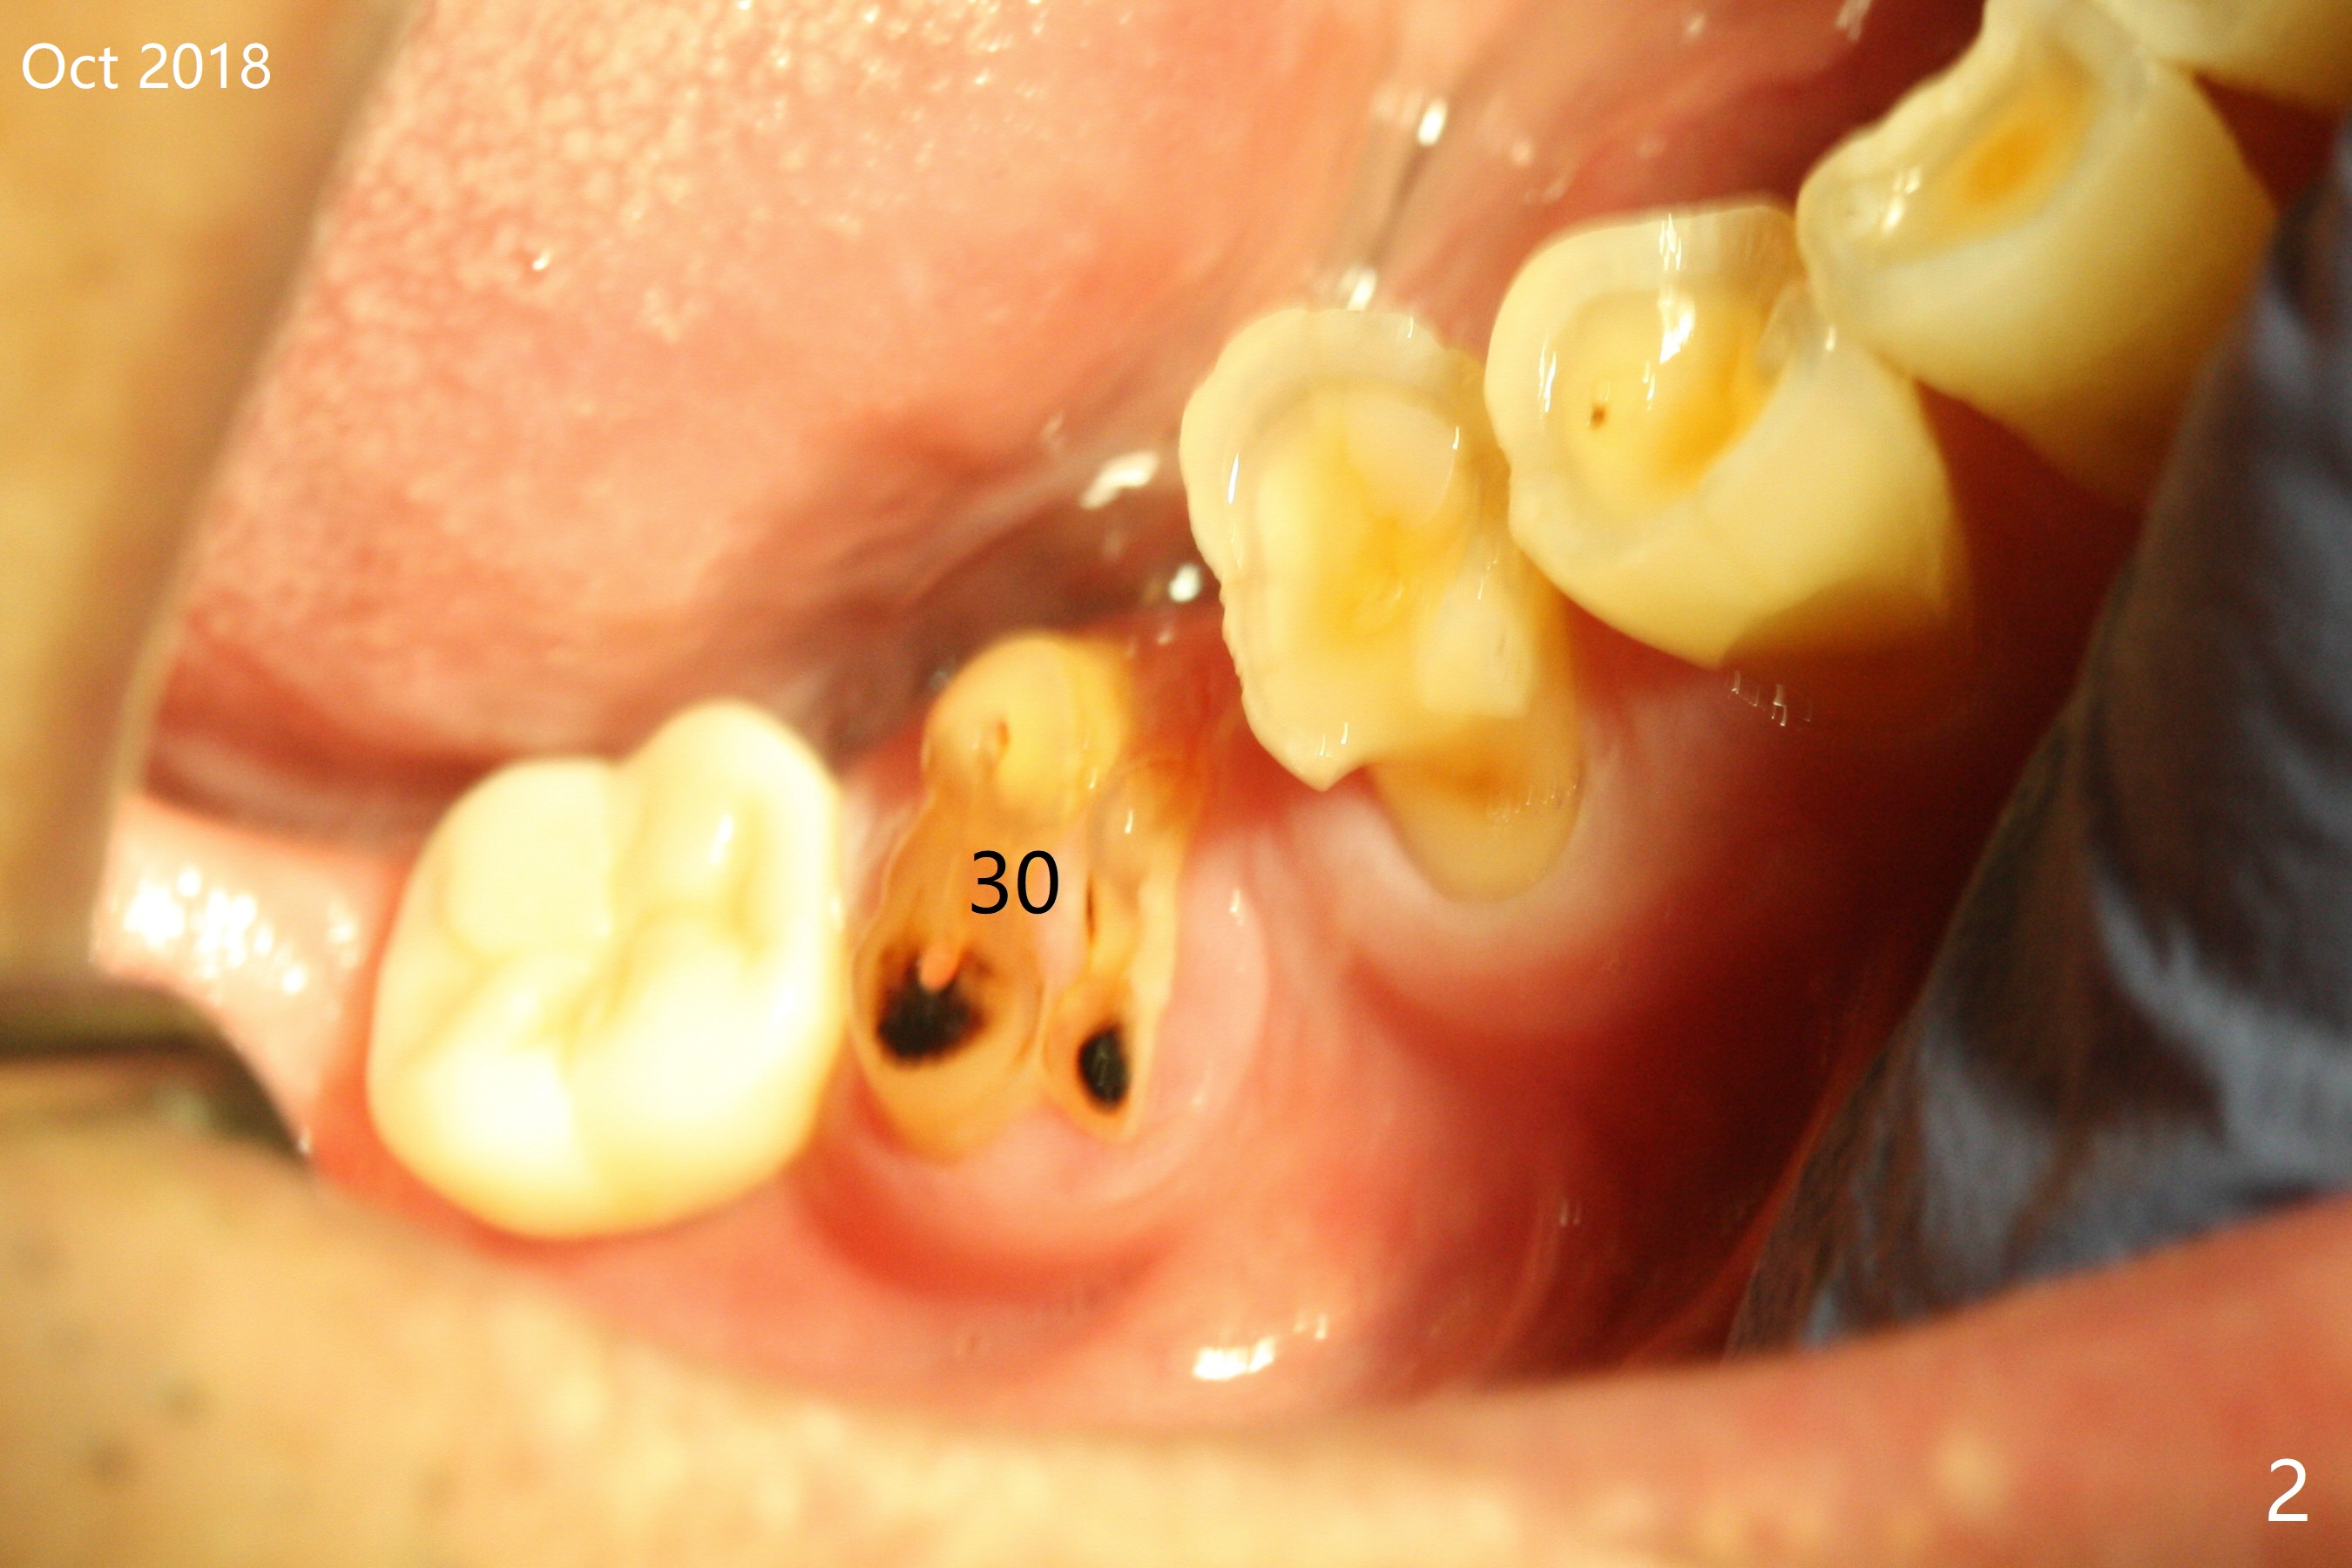

A 60-year-old man is a bruxer with severe occlusal wear (Fig.1-4). He requests implant to replace residual roots at #30 (Fig.4). A 5x11.5 mm implant will be placed. The abutment length should be limited because of limited crown height. An immediate provisional should be as low as possible.